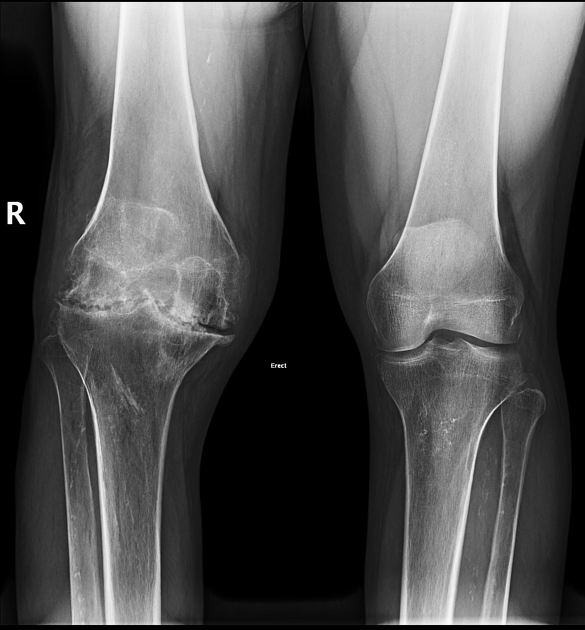

만성 혈우병성 관절병증으로 인한 통증은 상태에 따라서 발생될 수도 있으며 뼈에는 가골이 형성이 될 수 있으며 뼈의 밀도가 감소하여 골다공증이 발생합니다. 그리고 연골 간 공간이 매우 좁아지게 되며 관절면이 불규칙해집니다. 그러면서 관절의 변형이 나타날 수 있습니다.

반복적인 출혈로 인해 만성적으로 나타나는 관절의 구축 중 무릎 관절이 잘 펴지지 않게 하는 무릎이 굽혀진 상태로의 구축은 일상생활 동작의 제한을 일으키게 되는 가장 중요한 문제 중 하나입니다. 이를 개선하기 위해 보존적 요법으로 물리치료적인 방법을 시도하고 개선이 안 될 시에는 수술적인 요법을 실시하게 됩니다.